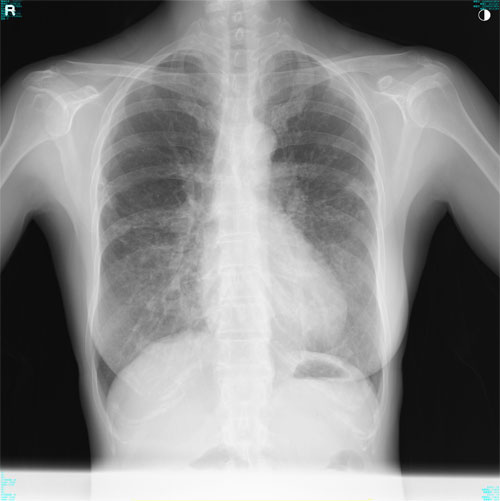

肺X線画像

- 2023.08.03 肺炎後の要観察(1)(国立系病院)